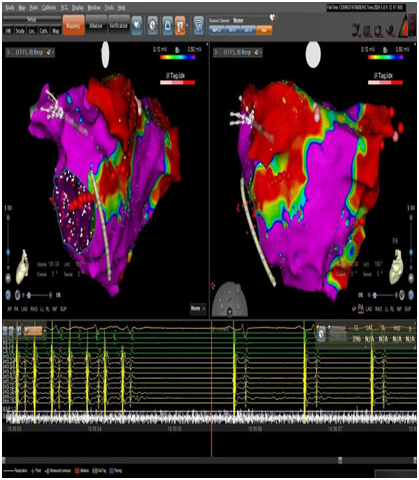

▲房扑终止

手术中通过电生理检查

找到“罪魁祸首”——

沈先生的心外膜Marshall静脉

参与并维持着心房颤动、心房扑动反复发作

冯振勤主任医师、赵波副主任医师

凭借丰富的临床经验和娴熟的手法

先完成

心脏Marshall静脉的无水乙醇化学消融

再完成

经导管心房肺静脉心内膜联合射频消融

进行彻底的病灶阻滞

每分钟130次的心房扑动节律终止

心电为每分钟70次的窦性心律

胸闷、心悸症状明显缓解